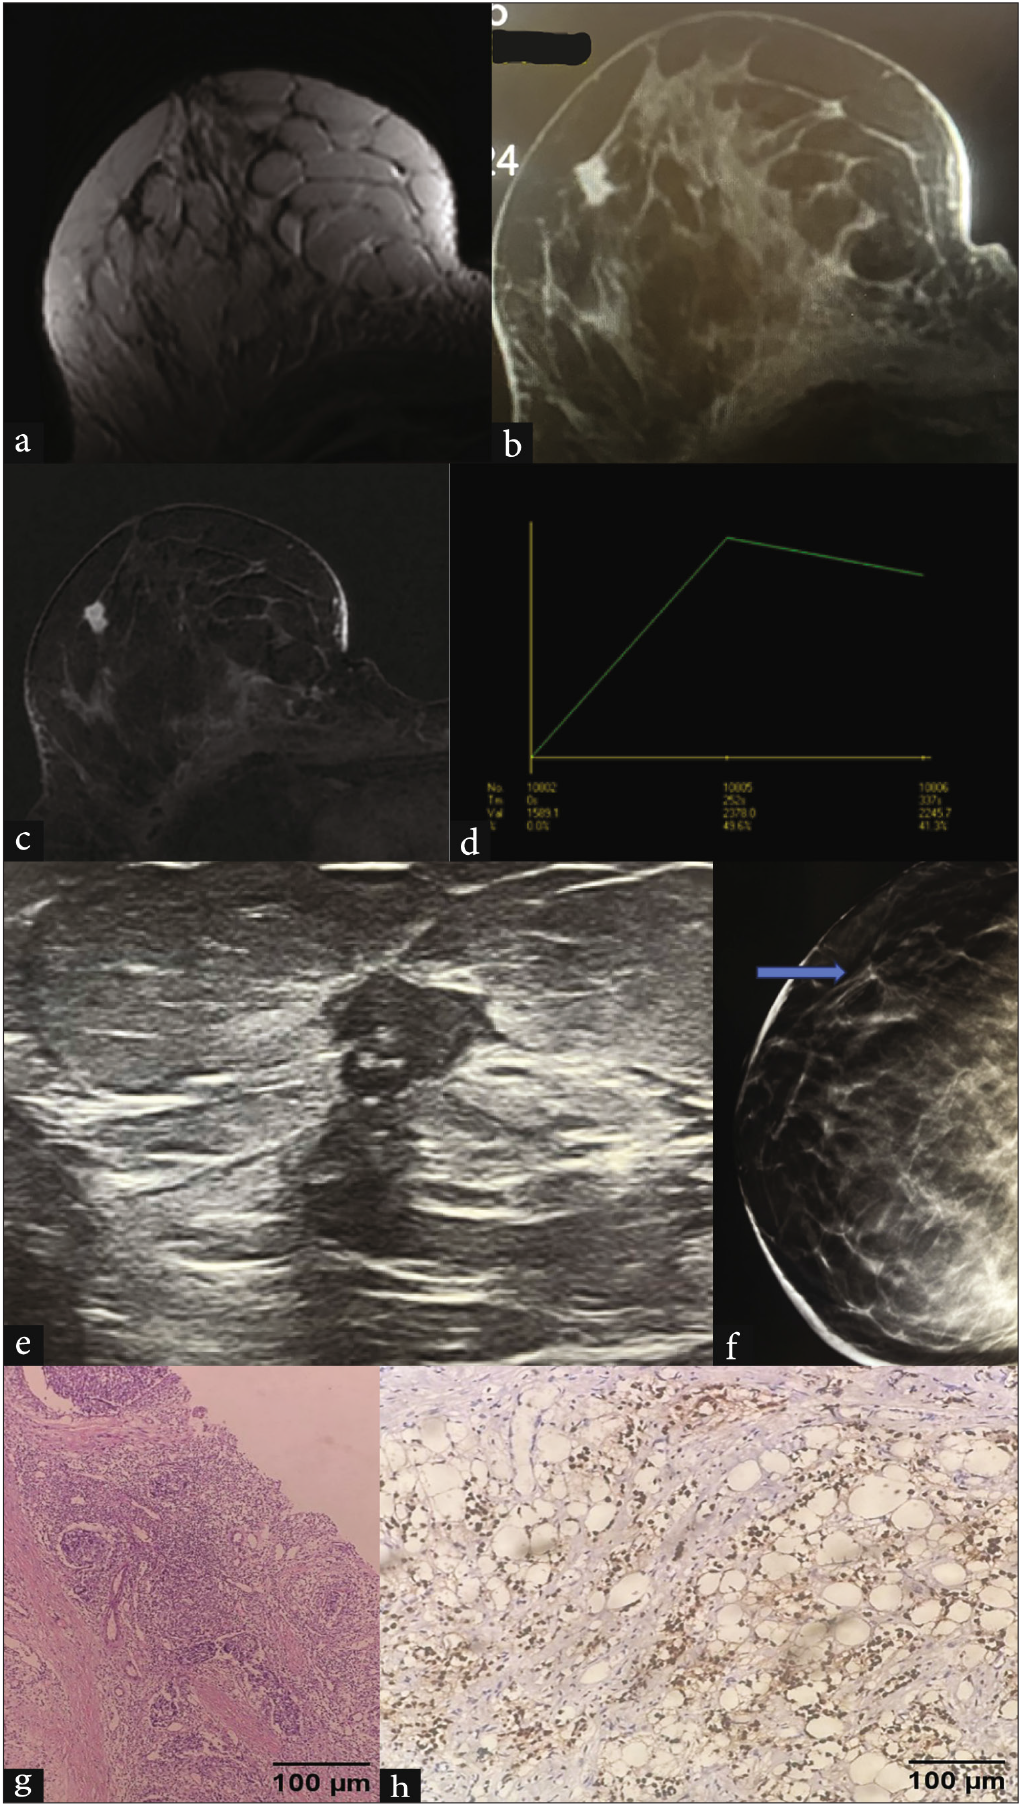

- Vague pain as presentation in 39 year old female: Dynamic contrast enhanced MRI revealed an irregular spiculated mass in upper outer quadrant of right breast which was hypointense on (a) T2 and showed heterogeneous enhancement on (b-c) post contrast images with (d) type III kinetic curve. (e) The corroborative USG showed mass as irregular, non-parallel, heterogeneous, spiculated and with no posterior features. It was seen as an area of architectural distortion better appreciated on (f) tomosynthesis. (g) Biopsy confirmed it as invasive ductal carcinoma, NST. H&E, 20x: Photomicrograph showing nests and sheets of tumor cells exhibiting marked nuclear pleomorphism, enlarged nuclei with vesicular chromatin, and increased mitosis—grade 3 invasive breast carcinoma, NST. (h) IHC for ER and PR, 10x: shows ER+/PR+ (Allred score 5 + 3 = 8). MRI: Magnetic resonance imaging, USG: Ultrasound, H&E: Hematoxylin and eosin, IHC: immunohistochemistry, NST: Non specific type, ER: Estrogen receptor, PR: Progestreone receptor.

TNBC can present as a rounded circumscribed mass with posterior enhancement, which are features of benign tumors. Figure 5a shows a well-circumscribed solid cystic mass with posterior acoustic enhancement. BIRADS 4C category was assigned by USG on the basis of the sudden increase in size of the lesion and the presence of suspicious ipsilateral lymph nodes. The lesion came out to be invasive ductal carcinoma, grade 3, TNBC. Figure 6 shows a similar oval-shaped mass lesion with circumscribed margins, internal cystic spaces, and posterior enhancement. Due to the chronicity of the lesion and absence of suspicious lymph nodes, a BIRADS category of 4B was assigned on USG. The lesion turned out to be a benign phyllodes tumor on histopathological examination (HPE).

- A 25-year-old female presented with a rapidly growing lump in the right breast associated with pain. (a) A grayscale ultrasound of the right breast shows a large, rounded, circumscribed, solid-cystic mass with associated posterior enhancement. (b) The CC view of the mammography shows a large rounded high-density lesion with circumscribed margins occupying all quadrants of the breast. CC: Cranio-caudal.